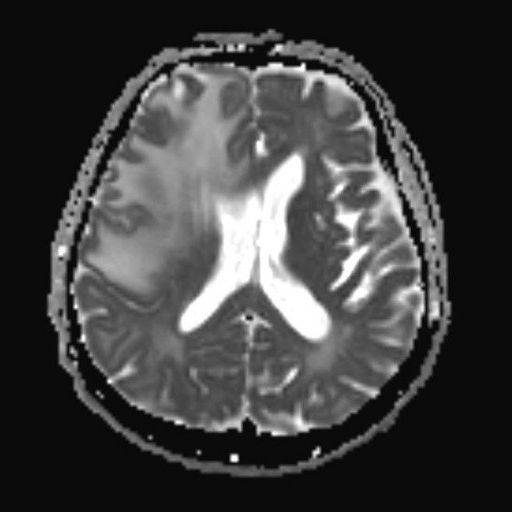

- C) Gradient seride milimetrik hemosiderin kalıntıları ve süperfisyal siderozis (kırmızı ok)